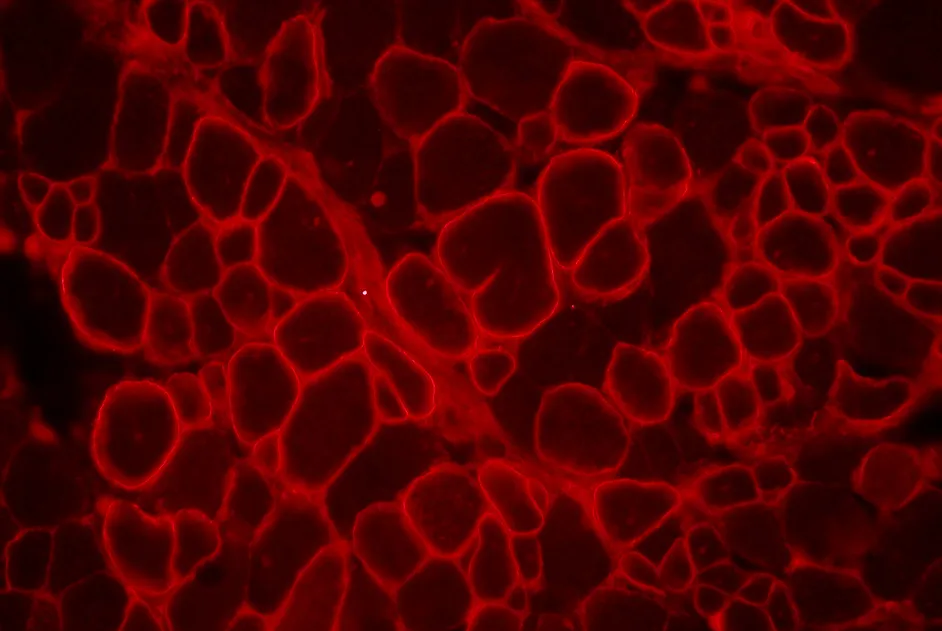

Une équipe américaine a mis en évidence une nouvelle molécule, le nabumétone, qui augmente l’expression de l’utrophine dans des cultures de cellules